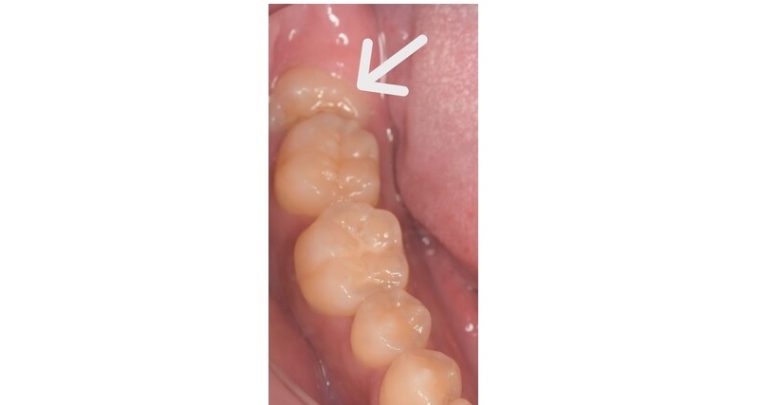

CASE 15

基本情報

| 年齢・性別 | 27歳・男性 |

| 主訴 | 左上の歯ぐきが痛い |

| 抜歯期間 | 30分 |

| 抜歯費用 | 約2,500円 別途CT撮影で3,000円 (2022年8月現在) |

| 抜歯内容 | 左上親知らずの半埋伏抜歯 |

| 治療方針 |

左上親知らずに数日前から痛みがあるとの事でした。親知らずと歯肉の間に細菌がたまり、歯肉が炎症していました。 レントゲンでは完全萌出してるように見えますが、実際は半分歯ぐきに覆われていました。今回は歯ぐきを切開して抜歯しました。 抜歯後はお痛みはなく会話もできて、いつも通りの生活を送れたとのことです。 |